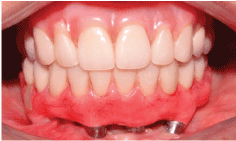

访问期间,增加成交量中观察到的后区右侧下颌骨和流动性在该地区的最末端的植入物,它是不可能的诊断是否产生的流动性被植入或下颌骨折(图1)。图像检查后,在皮瓣嵴处观察到一条透光线,一直延伸到种植体基底处,这表明下颌骨骨折无碎片脱离。我们还可以观察到,这是一个骨高度小的下颌骨,除了一个外,其他种植体显示边缘骨丢失(图2和3)。

图1:患者第一次就诊时的临床情况,在左侧下颌骨后区可以观察到缺乏种植体。

15天后进行临床对照,进行新的咬合调整和检查螺钉扭矩。3、6和9个月后进行临床对照,12个月后进行临床和x线片对照。在所有这些对照和图像中,观察到临床正常(图7和8)。

图7:临床方面显示种植体的排列,减少悬臂和种植体周围软组织的正常方面。